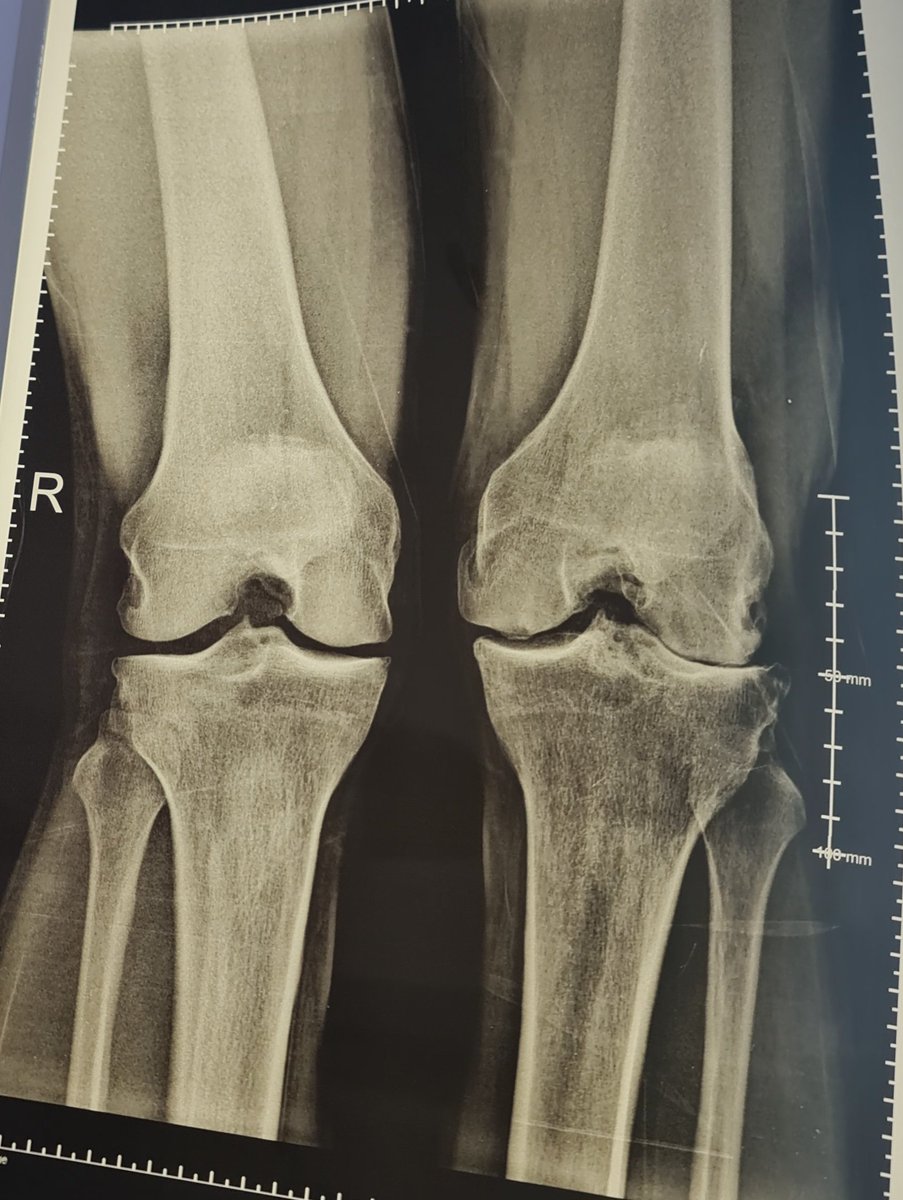

@hjluks 49 M , lt knee menisectomy 2002 and ACL tear , mild pain after Sport , when I examined the right knee I found it even more unstable than left but no complain! , so

Bilateral ACL tear , menistomy in left knee and still running, playing football in age of 49